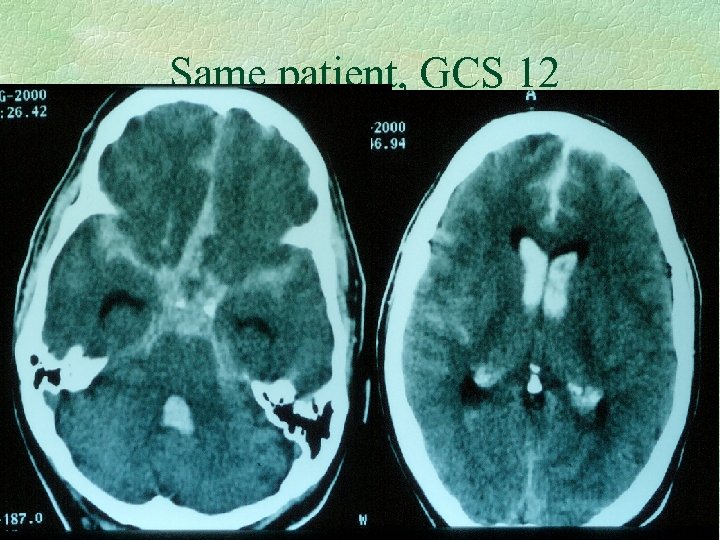

Diagnosis of SAH § CT : acute blood is white § LP - if and only if CT is normal l l best after 12 hours to allow xanthochromia experienced operator - traumatic tap problematic

Same patient, GCS 12

2 different patients